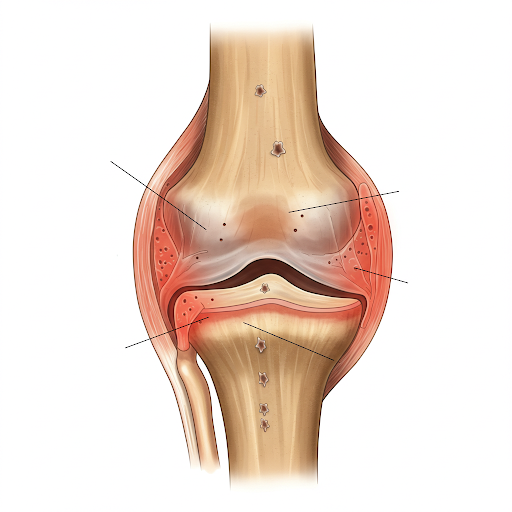

- 류마티스 관절염은 자가면역 질환입니다.

우리 몸의 면역 체계가 자기 관절을 공격해서 염증이 생기는 것이 원인입니다.

주로 30~50대 여성에게 많이 나타나며, 유전적 요인도 작용합니다. - 퇴행성 관절염은 노화나 과사용으로 인해 관절 연골이 닳아 생기는 질환입니다.

✔ 증상 차이

| 주요 증상 | 관절 붓기, 열감, 아침에 손가락이 뻣뻣함 (30분 이상) | 무릎, 허리 등 관절 통증, 움직일수록 심해짐 |

| 통증 위치 | 손가락, 손목, 팔꿈치 등 작은 관절부터 양쪽 대칭적으로 | 무릎, 허리, 고관절 등 큰 관절, 한쪽에 국한되기도 함 |

| 발병 속도 | 갑작스럽게 진행되는 경우가 많음 | 천천히 점진적으로 진행 |

| 염증 유무 | 염증 심함 (혈액 검사로도 확인 가능) | 염증은 거의 없음 |